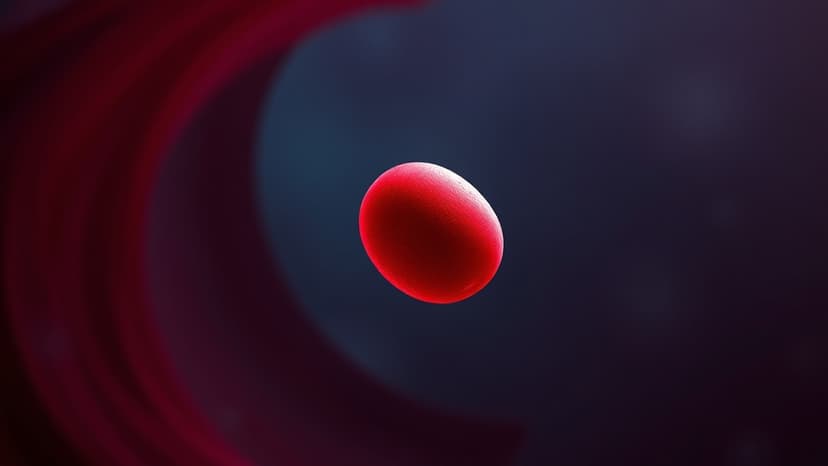

At just two years old, Hudson Reid from Kilwinning, Ayrshire, faced a life-threatening stroke. His mother initially mistook his symptoms for a bug, but his deteriorating condition led to a hospital visit where he was diagnosed with a blood clot and bleeding in his brain. Doctors attributed the stroke to severe dehydration causing his blood to thicken.

Hudson remained unconscious for five days and spent four weeks in the hospital. He received blood transfusions and was treated with blood thinners. Although medical professionals prognosticated that he might never walk or move again, Hudson defied expectations by walking within a week of the stroke.